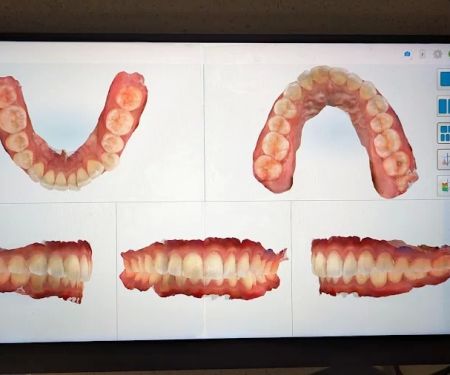

Dr. Anthony Nguyen Photos